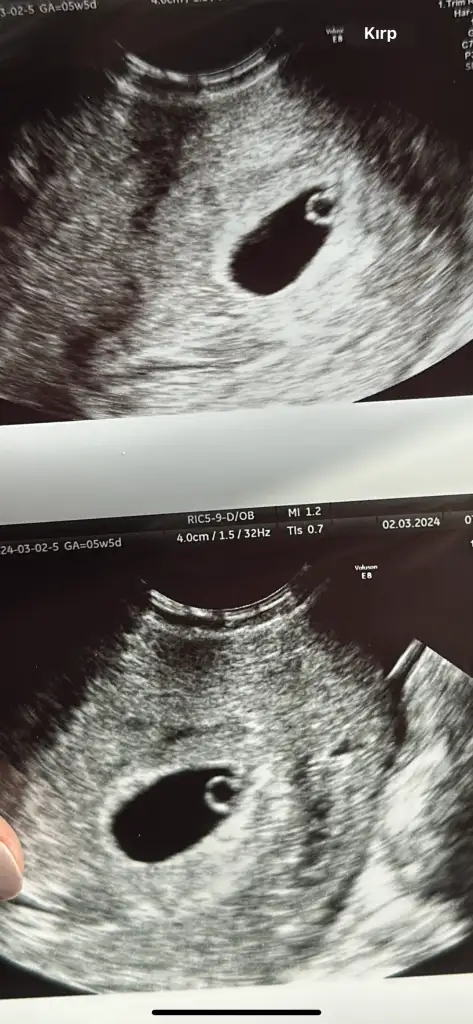

Ultrason görüntüsünü de ekliyorum anlayan olursa belki

Normalde 7+5 bugün ama ultrasona göre bebek 6+5 dedi